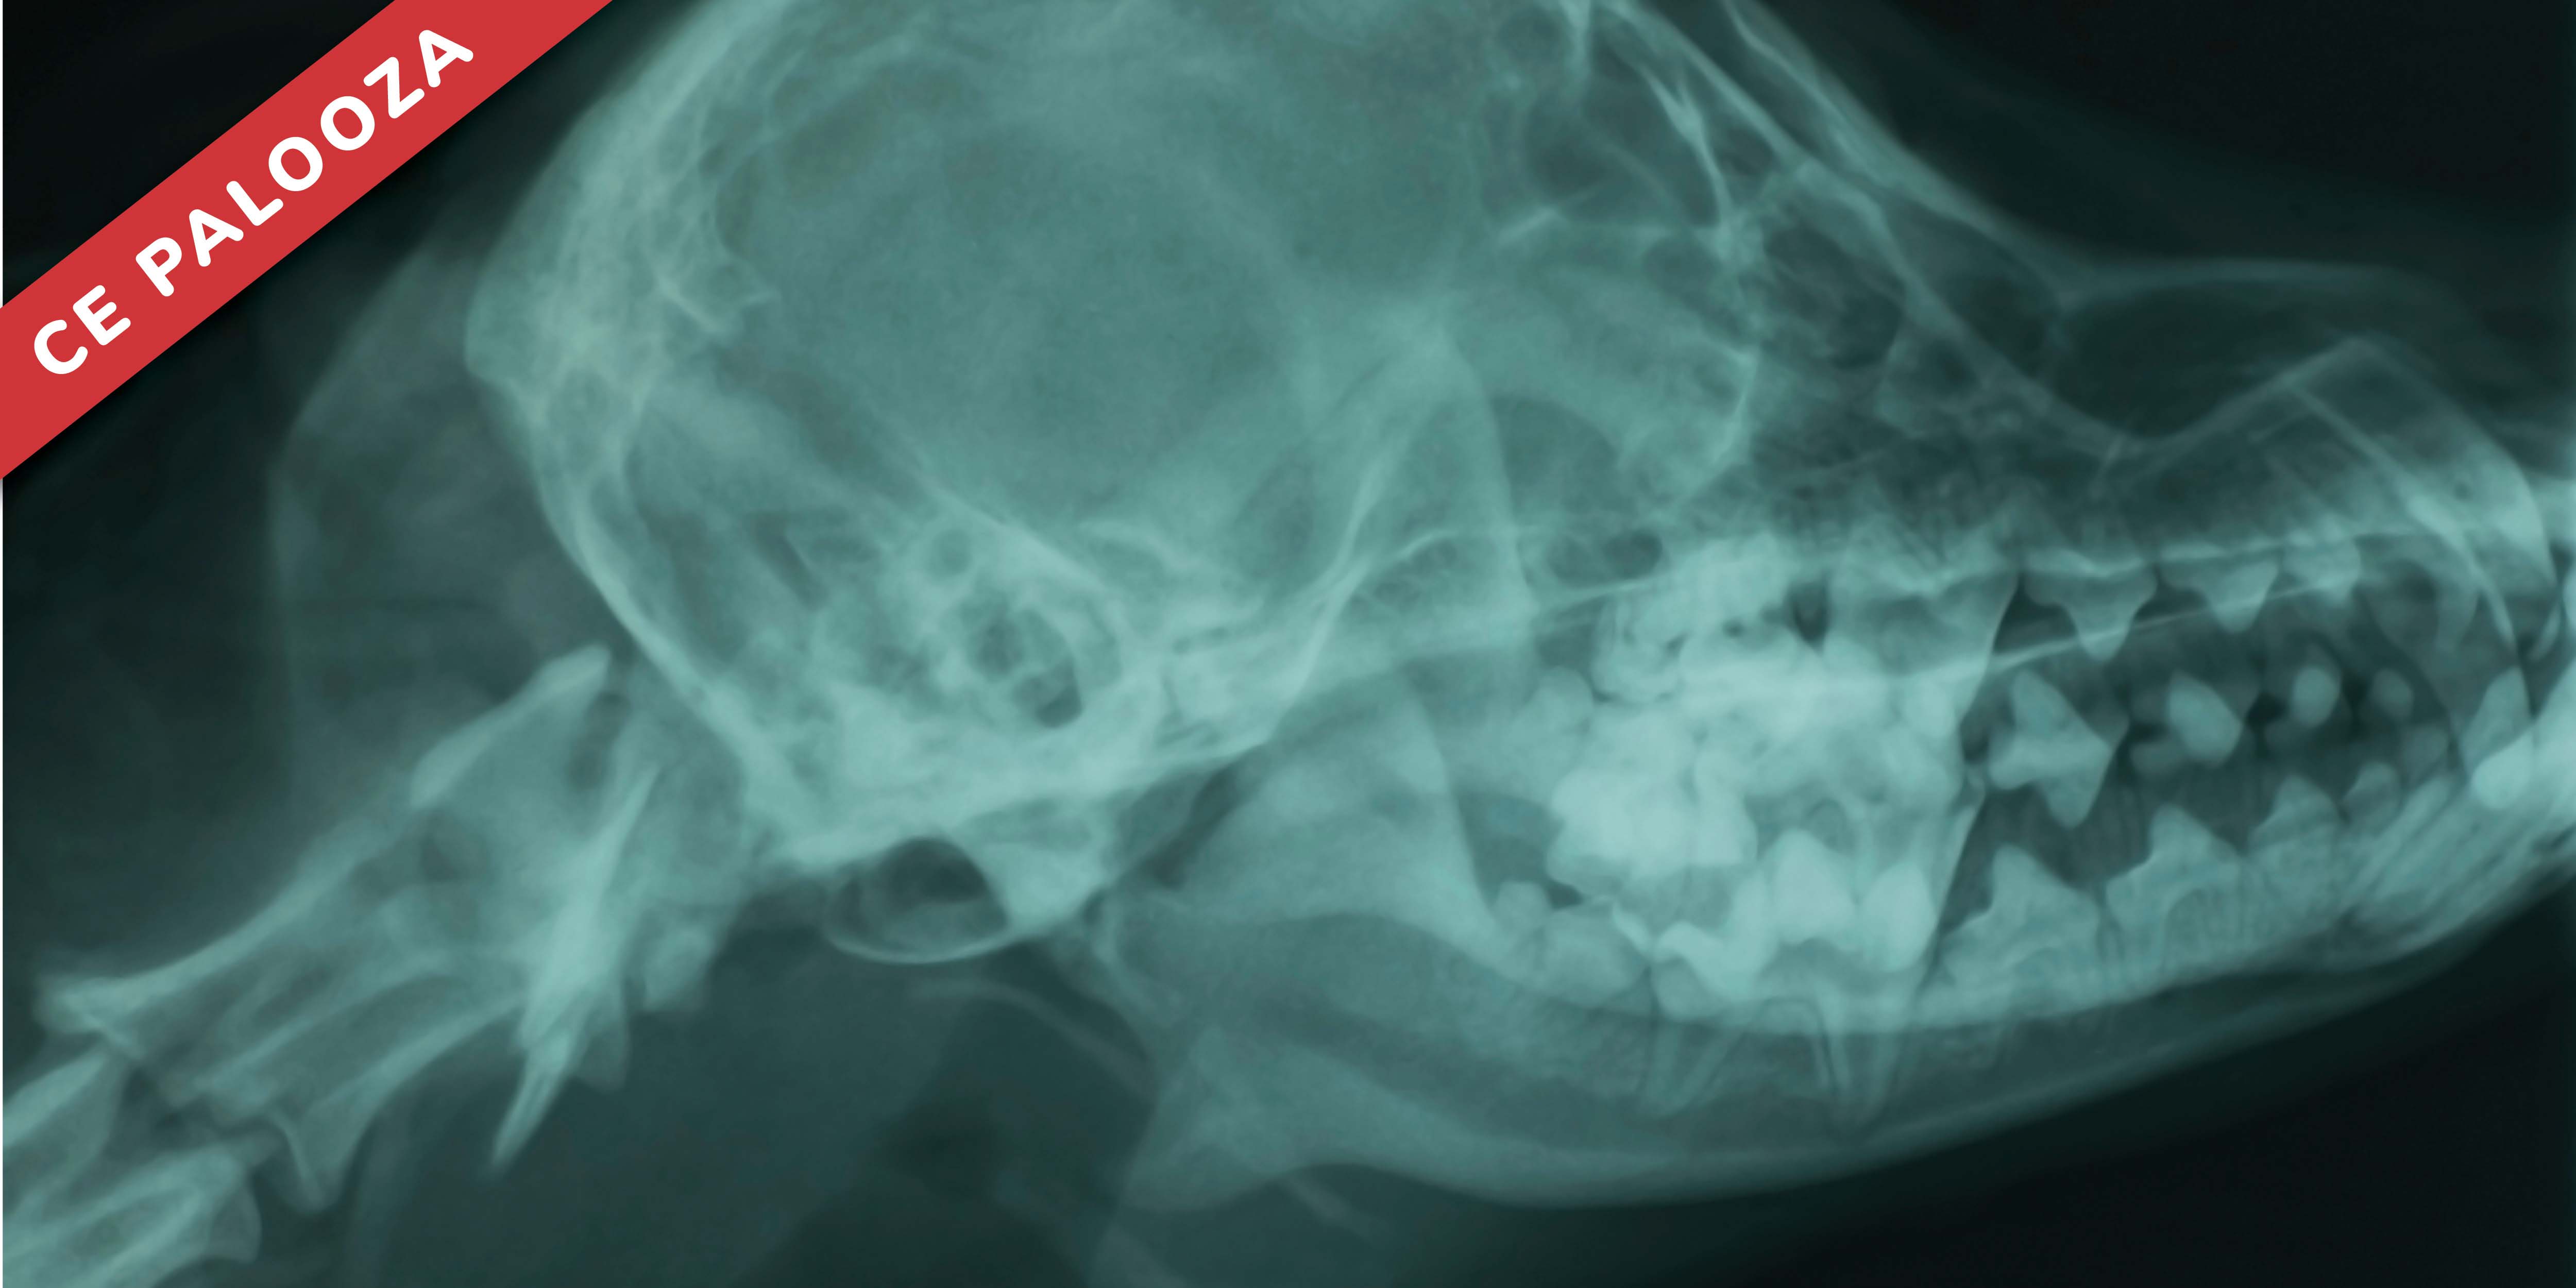

Common Challenges with Dental Radiographic Interpretation and Positioning

This webinar offers veterinarians a practical overview of intraoral dental radiography, covering its indications, interpretation, and role in clinical decision-making. It highlights how radiographs can reveal subgingival pathology invisible during oral examinations, improving diagnosis and client communication. We'll review normal anatomy and common radiographic findings, such as bone loss, periapical lesions, root pathology, and tooth resorption in cats and dogs. Practical tips are provided for using radiographs in treatment planning, estimating procedural complexity, and confirming extractions through pre- and post-procedural imaging. The presentation concludes with recommendations for case documentation, ongoing monitoring, and client education to improve care quality and build trust.